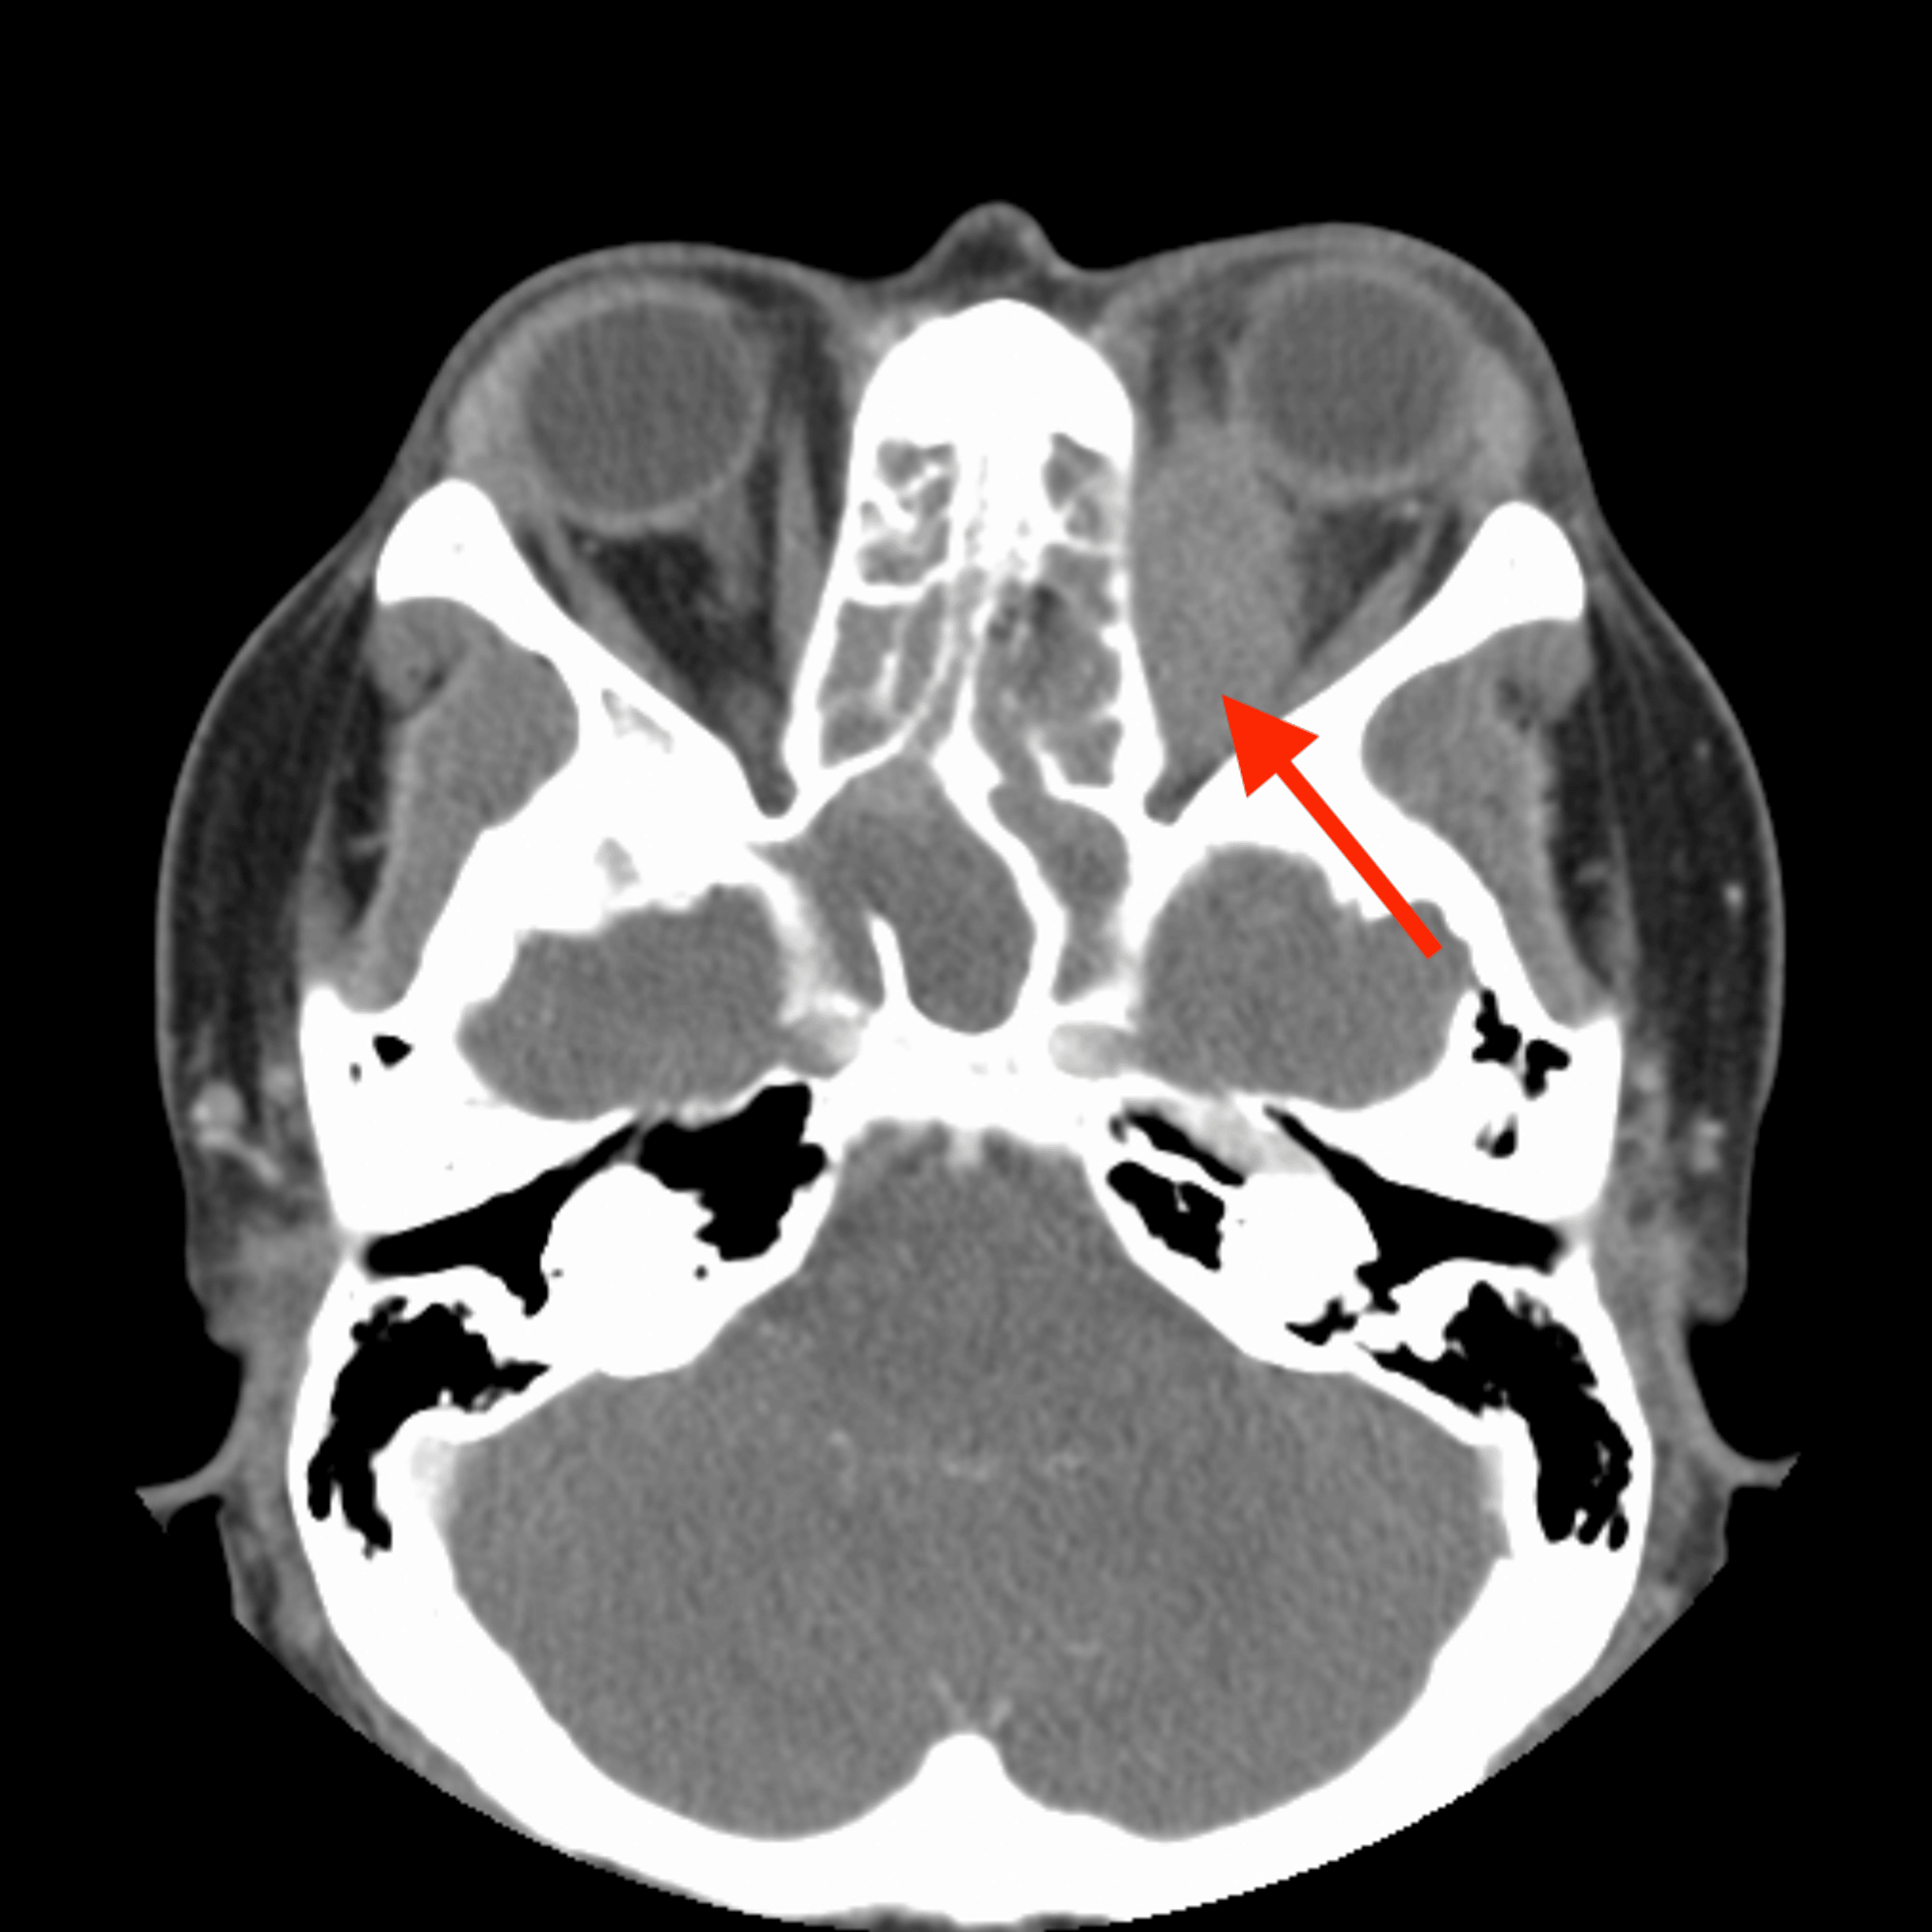

Axial computed tomography image through the face (bone windows) The BMJ Facial Bones With Contrast Ct Here is an overview of the indications for contrasted ct: Groove for the middle meningeal artery. By providing detailed visualizations of the bones, teeth, sinuses, and surrounding soft tissues, ct maxillofacial imaging aids in. A ct of the head is an exam that takes very thin slice images of the. What is a ct of the head, orbits, sinuses or. Facial Bones With Contrast Ct.